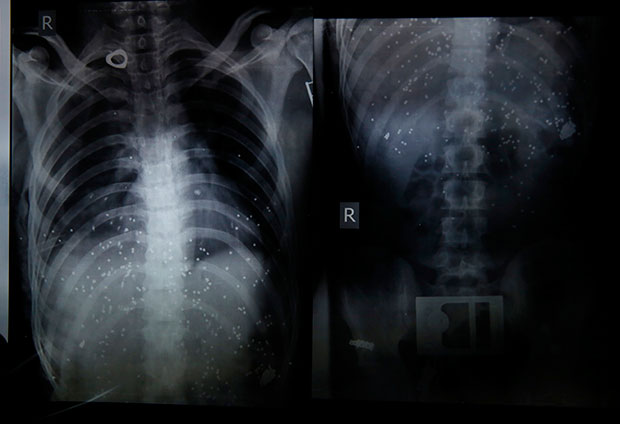

Sta Korona Cini Plucima Objavljeni Rendgenski Snimci Preminulih Ljudi

Procureli Rentdgenski Snimci Obolelih Od Korone Bele Senke Na Plucima Dovele Do Jakih Upala Foto Novosti Rs

Sokantne Fotografije Pokazuju Koliko Je Korona Virus Unistio Pluca Prvim Zrtvama Bolesti U Italiji Najnovije Vesti Srbija Danas

Korona Virus Je Poput Kombinacije Sars A I Aids A Pluca Preminulih Izgledaju Uzasno Telegraf Rs